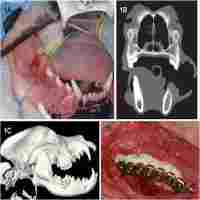

| Abstract | This study presents a comprehensive radiographic evaluation of bone regeneration within a pedicled muscle flap for the reconstruction of critical size mandibular defect. The surgical defect (20 mm×15 mm) was created in the mandible of ten experimental rabbits. The masseter muscle was adapted to fill the surgical defect, a combination of calcium sulphate/hydroxyapatite cement (CERAMENT™ |SPINE SUPPORT), BMP-7 and rabbit mesenchymal stromal cells (rMSCs) was injected inside the muscle tissue. Radiographic assessment was carried out on the day of surgery and at 4, 8, and 12 weeks postoperatively. At 12 weeks, the animals were sacrificed and cone beam computerized tomography (CBCT) scanning and micro-computed tomography (µ-CT) were carried out. Clinically, a clear layer of bone tissue was identified closely adherent to the border of the surgical defect. Sporadic radio-opaque areas within the surgical defect were detected radiographically. In comparison with the opposite non operated control side, the estimated quantitative scoring of the radio-opacity was 46.6% ±15, the mean volume of the radio-opaque areas was 63.4% ±20. Areas of a bone density higher than that of the mandibular bone (+35% ±25%) were detected at the borders of the surgical defect. The micro-CT analysis revealed thinner trabeculae of the regenerated bone with a more condensed trabecular pattern than the surrounding native bone. These findings suggest a rapid deposition rate of the mineralised tissue and an active remodelling process of the newly regenerated bone within the muscle flap. The novel surgical model of this study has potential clinical application; the assessment of bone regeneration using the presented radiolographic protocol is descriptive and comprehensive. The findings of this research confirm the remarkable potential of local muscle flaps as local bioreactors to induce bone formation for reconstruction of maxillofacial bony defects. |